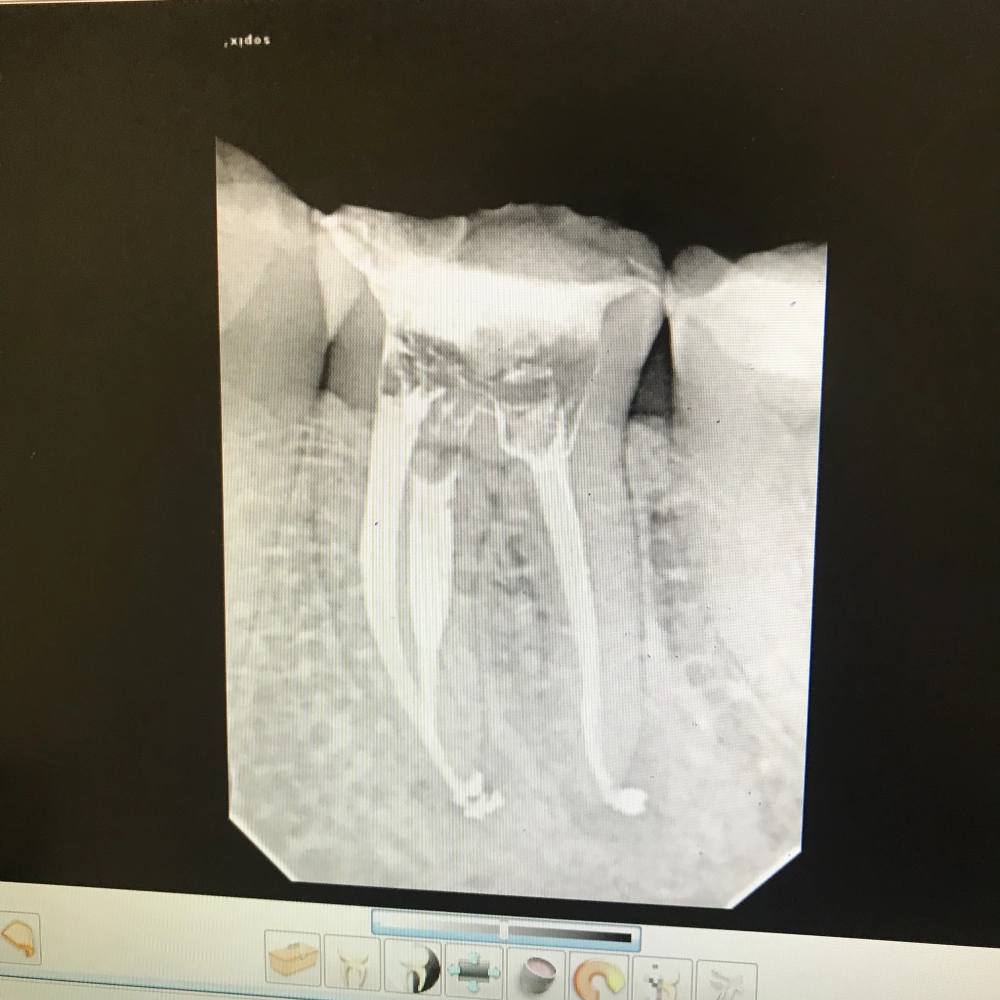

Лечение зубов под микроскопом

Современное лечение каналов зуба проводится с помощью операционного микроскопа.

от 10000 руб.